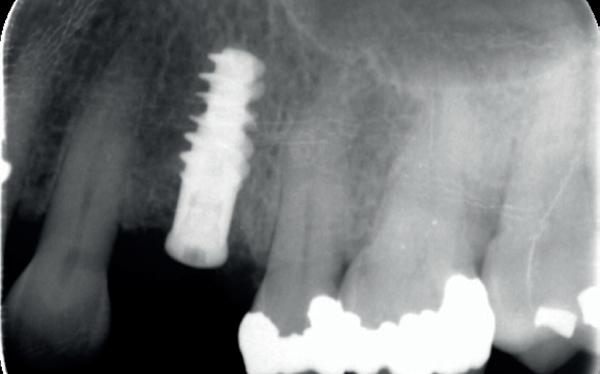

In deze casus is extractie van de 37 geïndiceerd in verband met een fistel en restpockets, zoals zichtbaar op de röntgenfoto’s (afbeelding 1). Duidelijk te zien is de forse peri-apicale ontsteking en het botverlies bij de 37, dat zowel richting buccaal als linguaal doorloopt. De 37 wordt atraumatisch verwijderd. Er is aan de linguale zijde veel bot verloren en er is sprake van een perforatie aan de buccale zijde.

Er wordt besloten om botmateriaal te plaatsen in de extractie-alveole. Vervolgens wordt het afgesloten met een titanium versterkt d-PTFE membraan (afbeelding 2). Na vier weken wordt het membraan verwijderd.

Zes maanden na extractie wordt het implantaat 37 geplaatst. Er is sprake van een goede genezing en de processushoogte en -breedte zijn behouden en opgebouwd. Ook is er zichtbaar gekeratiniseerd weefsel

1 2 Ridge preservation met d-PTFE membranen 35

gewonnen. De wond kan na het plaatsen van een healing abutment primair gesloten worden (Afbeelding 3a-3d).

In afbeeldingen 4a-c is het resultaat drie maanden na het plaatsen van het implantaat te zien. De genezing is volledig en de verwijzer kan de suprastructuur vervaardigen (afbeelding 4a-4c).

In afbeeldingen 5a-d is de implantaatkroon 37 te zien, twee jaar na plaatsing. Op de röntgenfoto is herstel van zowel corticaal als spongieus bot te zien. (De CB-CT was vervaardigd in verband met implantologische indicatie in het naastliggende gebied).